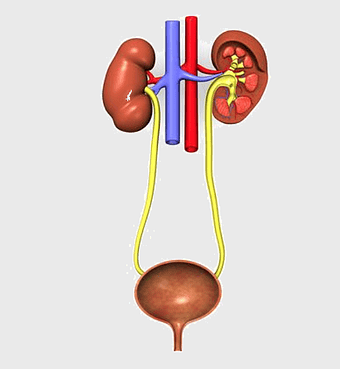

urinary system anatomy, kidney function illustration, ureter diagram, bladder infection symptoms, renal system health, excretory function chart, genitourinary medical diagram -

human excretory system diagram, kidney and bladder anatomy, urinary system function, renal arteries and ureters, human body organ systems, medical illustration of kidneys, biological diagram of excretory organs -